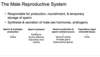

male repro system

responsible for?

synthesis and secretion of?